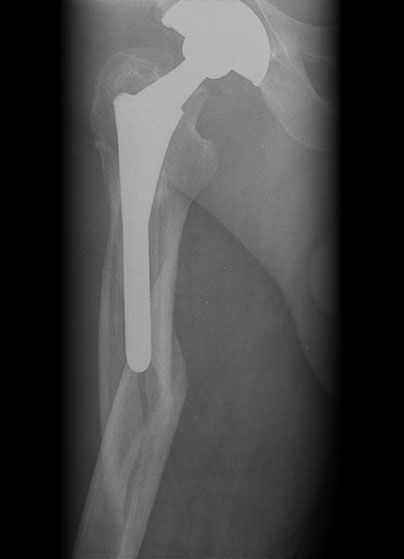

Failed THR